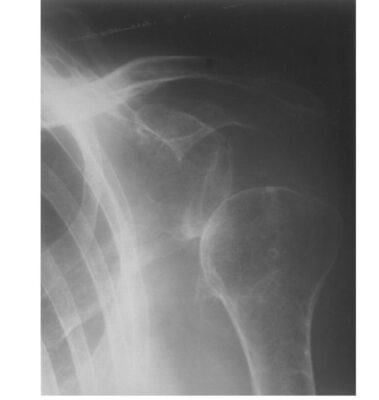

X quang khớp vai: đo mức bán trật khớp vai, xác định các bất thường ở xương như gãy xương